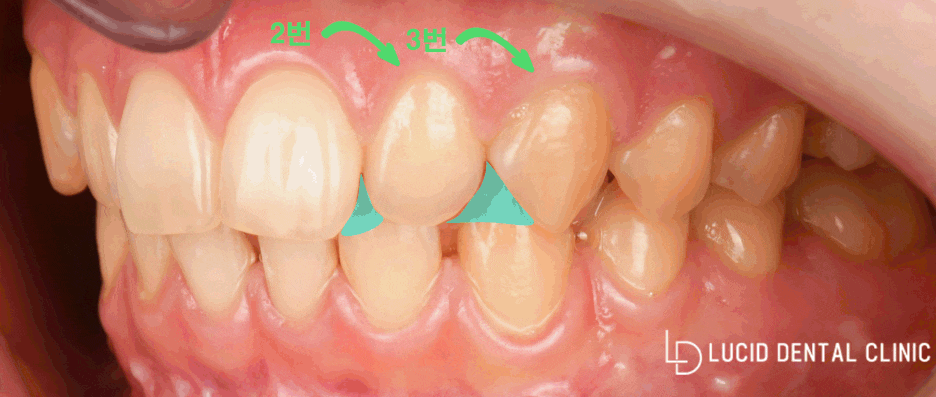

먼저 초진 사진 보겠습니다.

2번부터 3번이 interdental gap이

있는 걸 관찰할 수 있습니다.

즉 치간사이가 벌어져 있습니다.

그리고 또 변색이 한눈에 보이는데요.